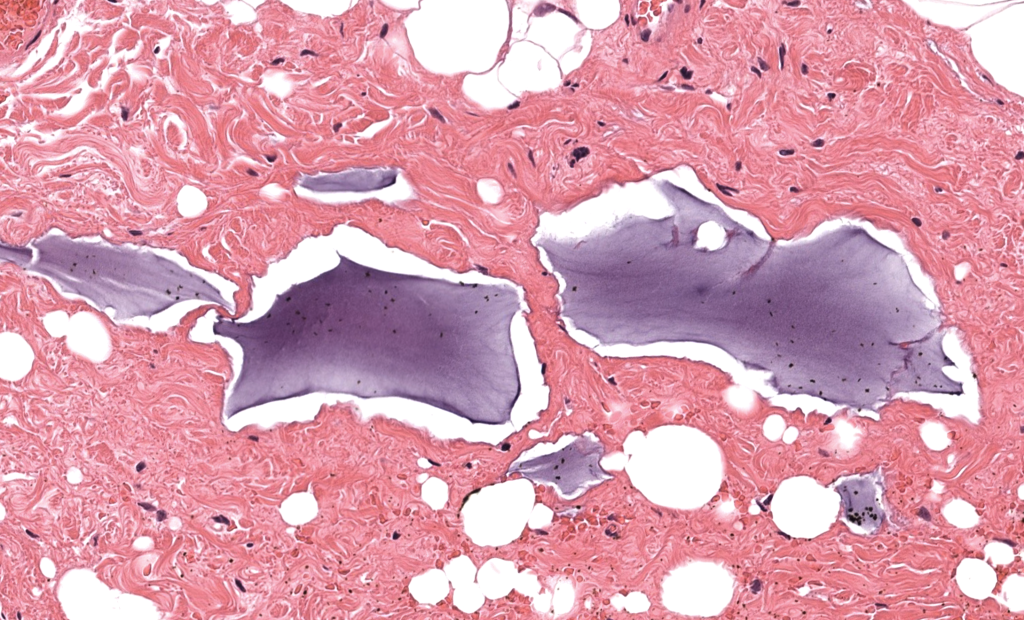

- Ácido hialurónico (HA): depósitos amorfo-basófilos tipo “lagos/placas” o seudocavidades, con reacción variable (a veces mínima). (El-Khalawany, 2015; Bhojani-Lynch, 2017)

- Silicona/aceites: patrón vacuolar tipo “Swiss cheese” con histiocitos y células gigantes; puede ser extenso y migratorio. (Schwartzfarb, 2008; Ellis, 2012)